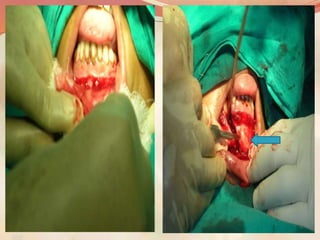

Fixation by miniplate and

reinforcement with

reconstruction plate and

bone grafting for gap

fracture.